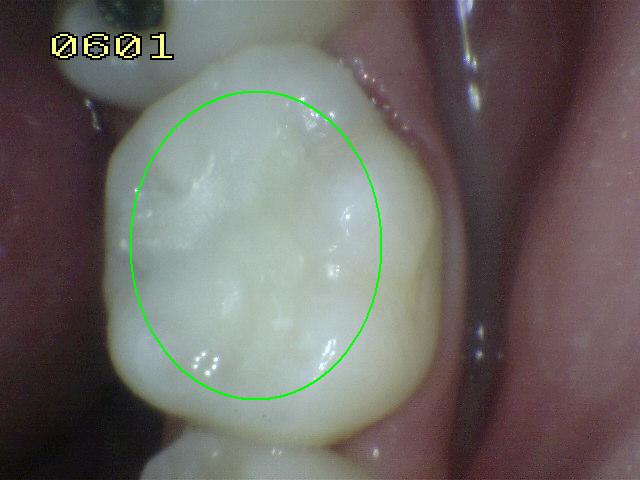

Código 0: No

hay evidencia de caries en esmalte seco.

- Una superficie dental sana

adyacente al margen de una restauración o sellante. No

debe haber evidencia de caries (ya sea que no presente o

que presente un cambio cuestionable en la translucidez

del esmalte después del secado prolongado con aire

durante 5 segundos).

- Las superficies con defectos

marginales de menos de 0,5 mm de ancho (es decir, no

entra la punta redonda de la sonda de la OMS); los

defectos de desarrollo, tales como hipoplasia del

esmalte; fluorosis; desgaste dental (atrición, abrasión

y erosión), y las manchas intrínsecas o extrínsecas se

registran como sanas.

- Los márgenes pigmentados

compatibles con hábitos no cariogénicos (por ejemplo,

beber té, mate o café frecuentemente) y que no presentan signos

compatibles con la desmineralización deben ser

clasificados como sanos.